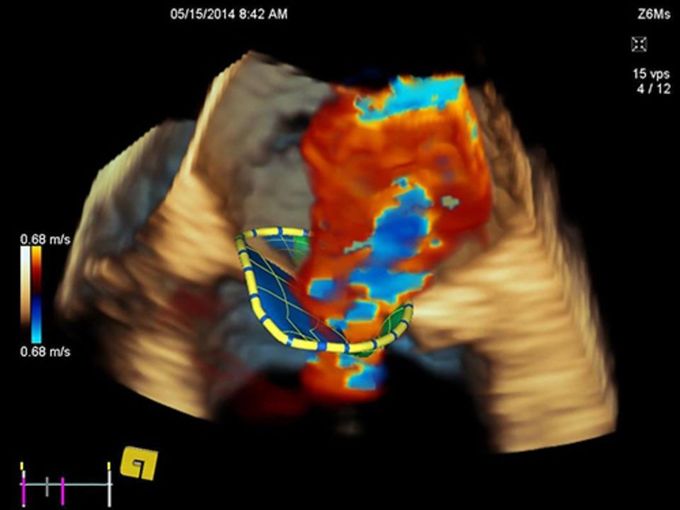

Кроме новой техники, можно заказать восстановленные медицинские системы: ультразвуковые сканеры, томографы, флюороскопы, ангиографы и хирургические установки С-дуга.